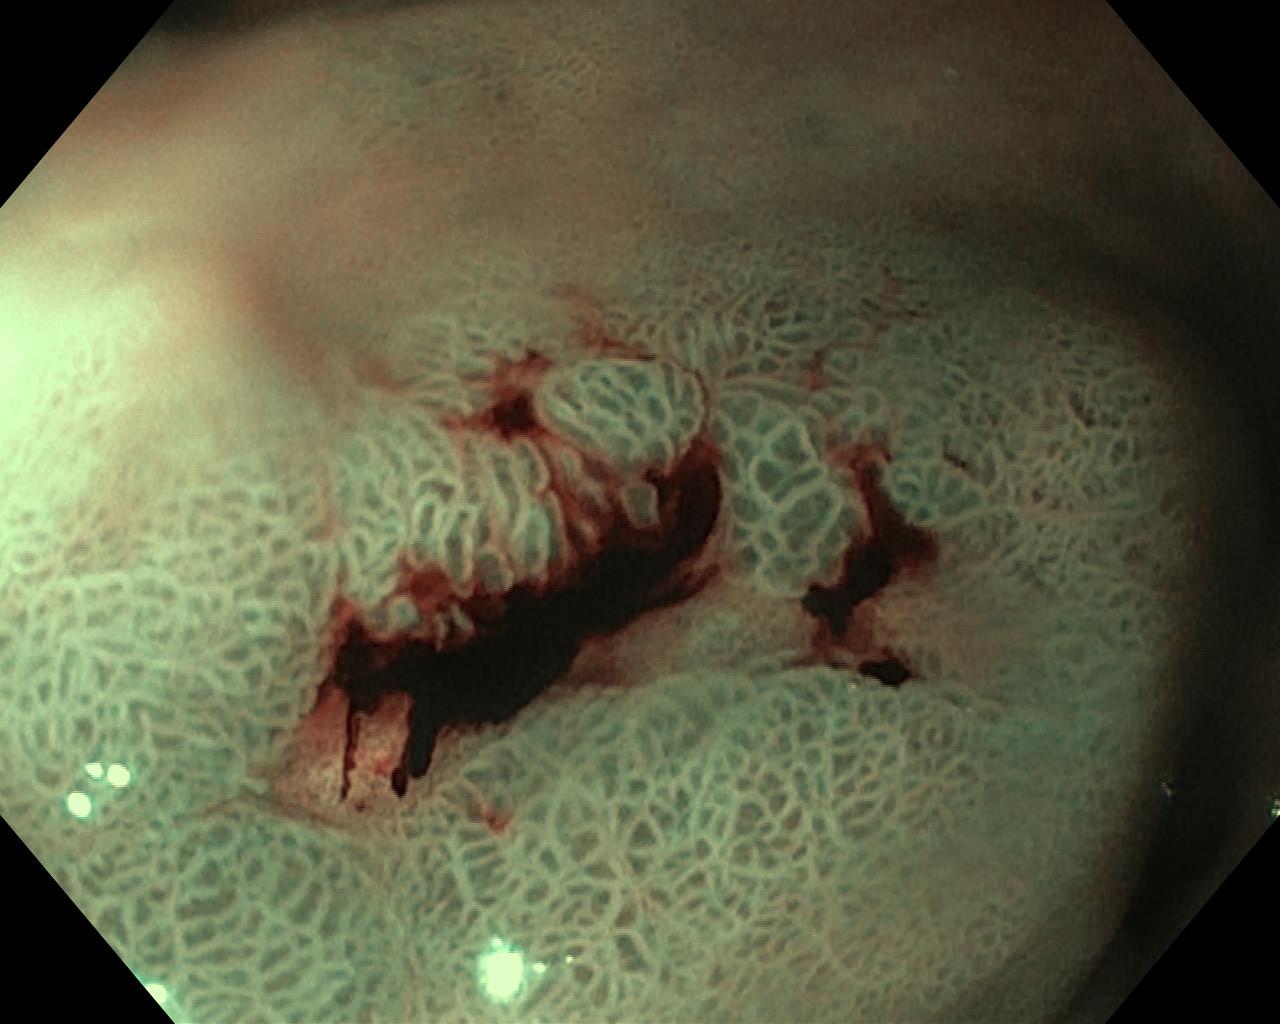

Krwawienie